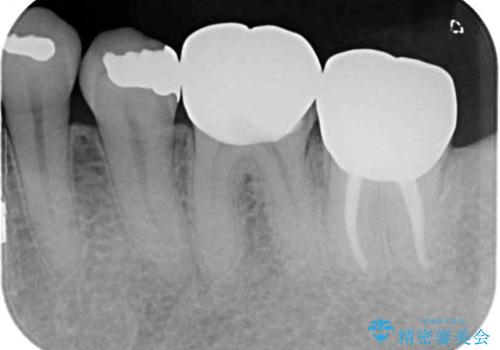

- 奥歯を他院で抜歯した後、インプラント治療を希望とのことで来院された患者様です。

ブリッジの支台を抜歯したことで2本のインプラントが必要であり、その後方はインプラント埋入に必要な骨量が不足していたため、上顎洞粘膜の挙上を行うこととしました。

また、残っている最後方歯は手前に倒れてきていたため、部分矯正により奥に移動させてから、インプラント埋入を行うこととしました。